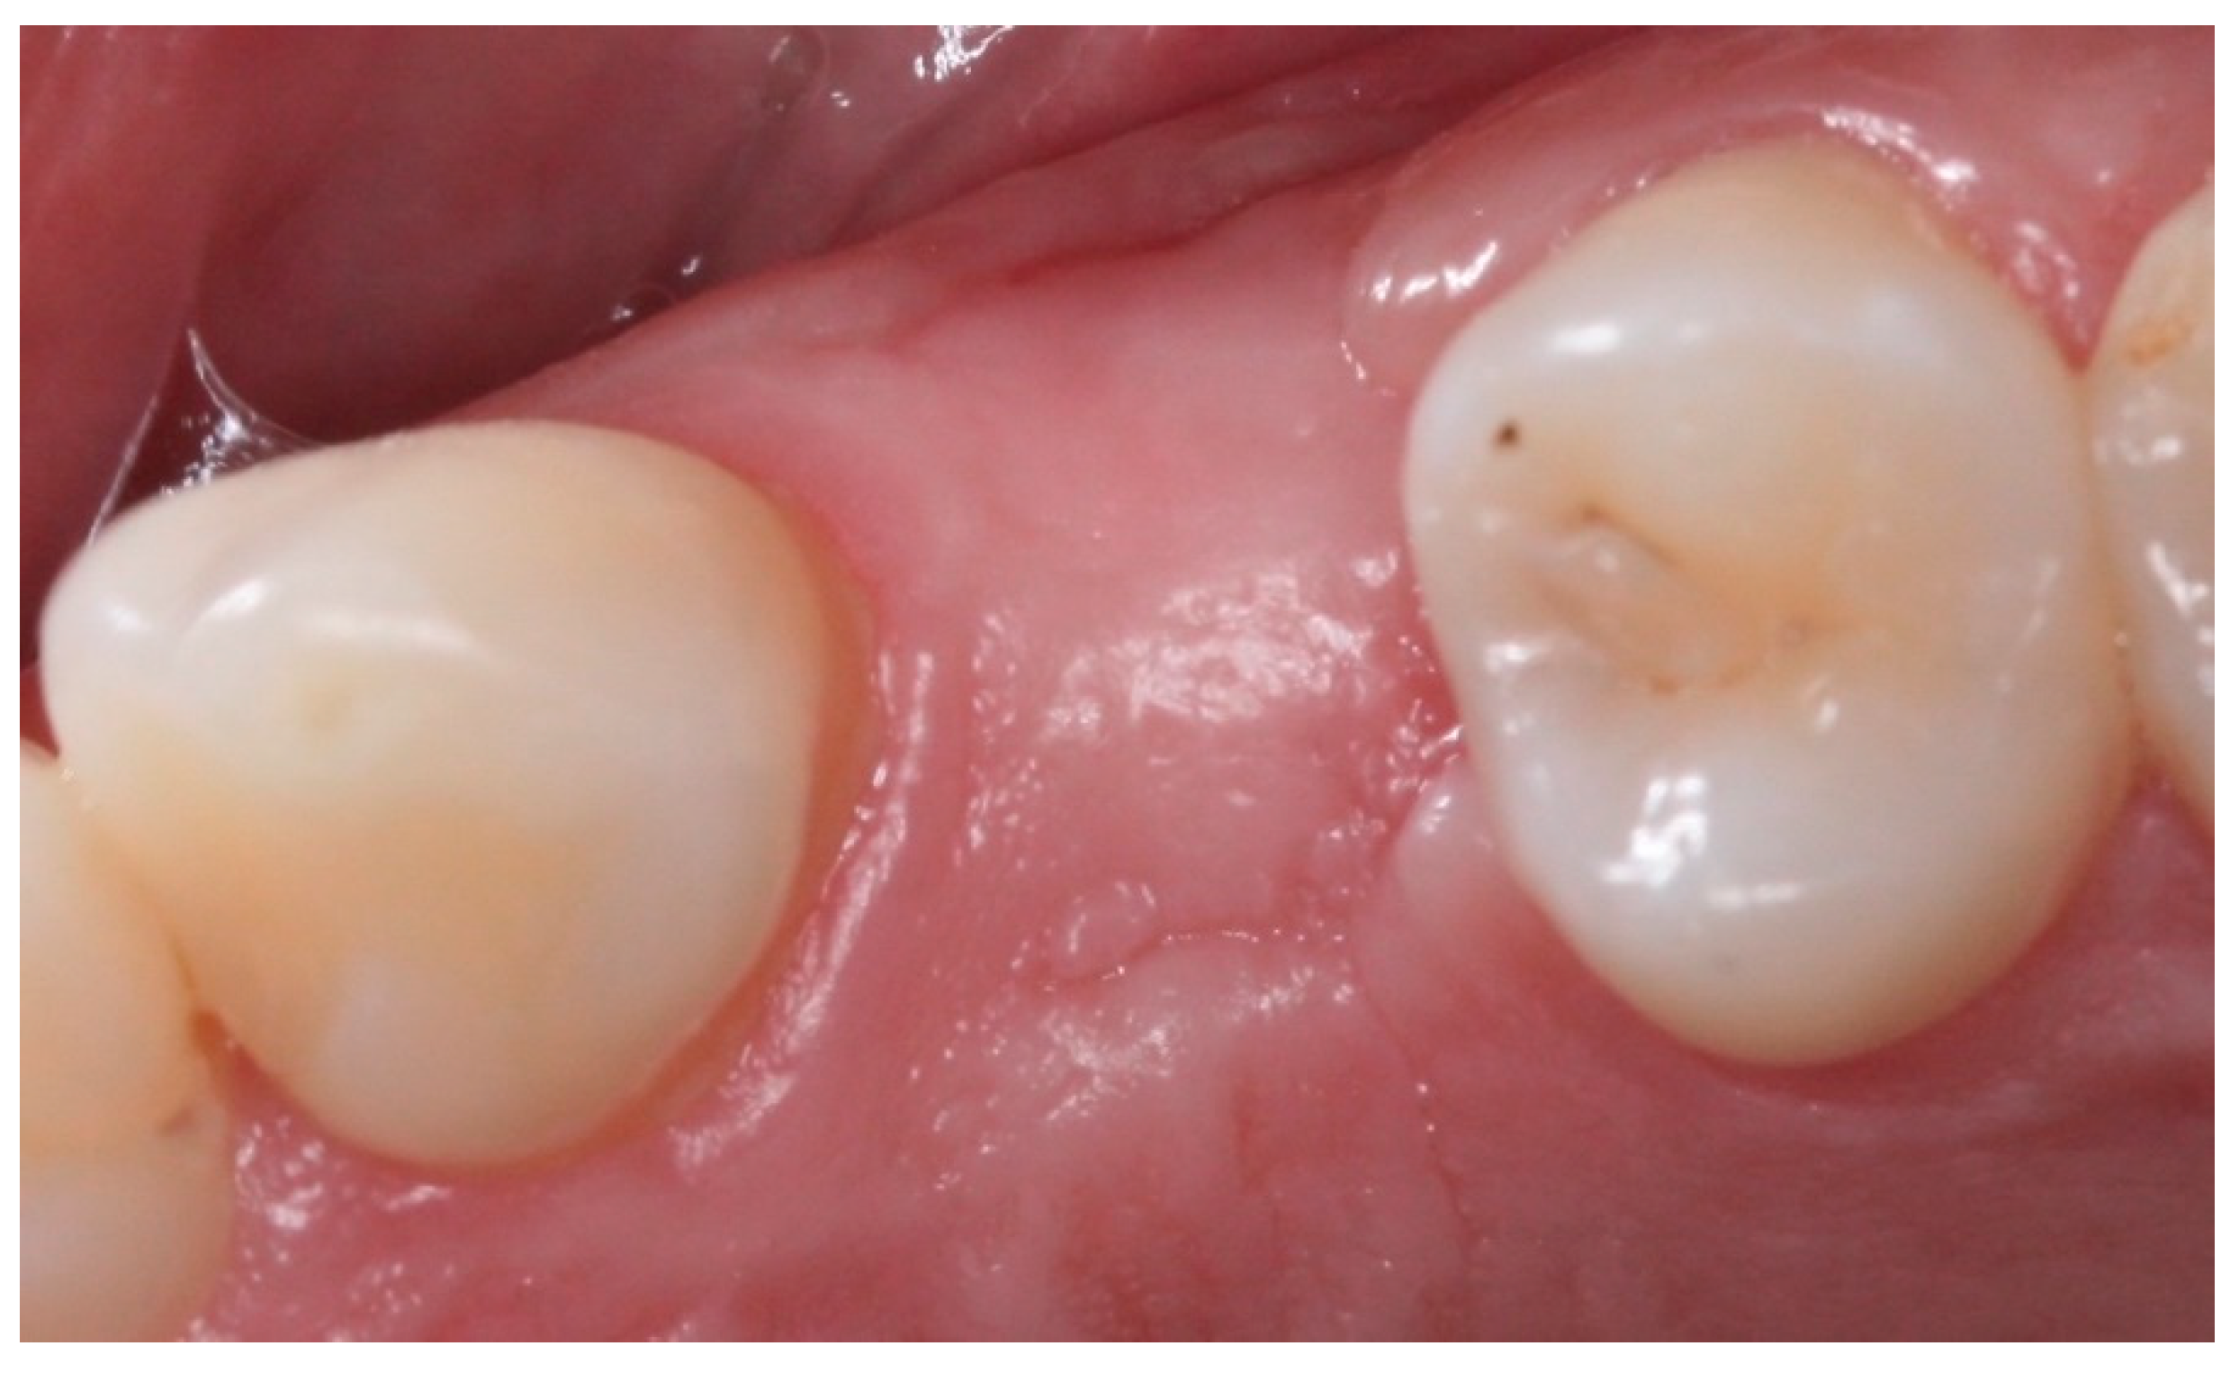

2.5. Post-Surgical Procedures

4. Conclusions